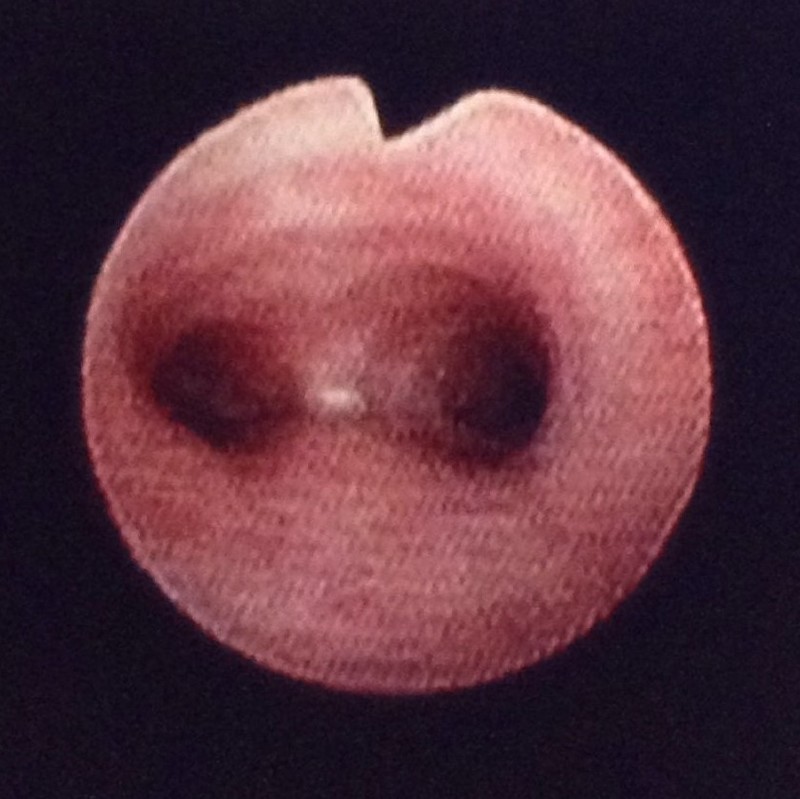

気管から気管分岐部(左右の主気管支入口) 提供:石立誠人先生

空気の通り道は、口から始まって胸の中央のあたりで左右の気管支に分かれ、その後は木のように細かく枝分かれしていきます。気管支鏡では、区域気管支の次の分枝である亜区域気管支という直径5mm程度の範囲まで内腔を確認することができます。